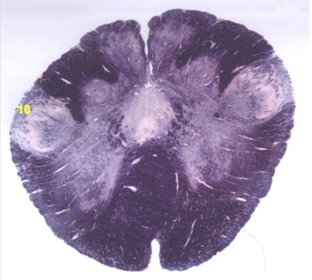

| Nucleus gracilis | |

| Accessory nucleus | |

| Medial longitudinal faciculus | |

| Pyramidal decussation | |

| Medullary pyramids | |

| Anterior spinocerebellar tract | |

| ALS | |

| Posterior spinocerebellar tract | |

| Spinal tract of V | |

| Spinal nucleus of V | |

| Nucleus cuneatus | |

| Fasciculus cuneatus | |

| Fasciculus gracilis | |

| Central canal | |